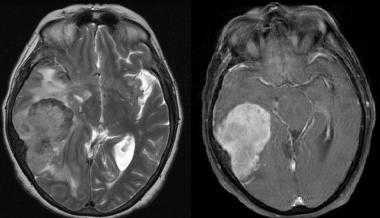

Менингиома лобной доли: КТ-картина. После введения контрастного вещества виден характерный вид «колеса со спицами» в структуре слабо контрастируемой опухоли. Несмотря на то, что данный паттерн чаще наблюдается при ангиографии, он также отмечается на томографических изображениях.

МРТ того же пациента, выполненная после предыдущей КТ: аксиальное Т1-взвешенное изображение после введения гадолиния и аксиальное Т2-взвешенное изображение. Видна крупная менингиома лобной области, расположенная срединно, со специфическим паттерном «колеса со спицами».